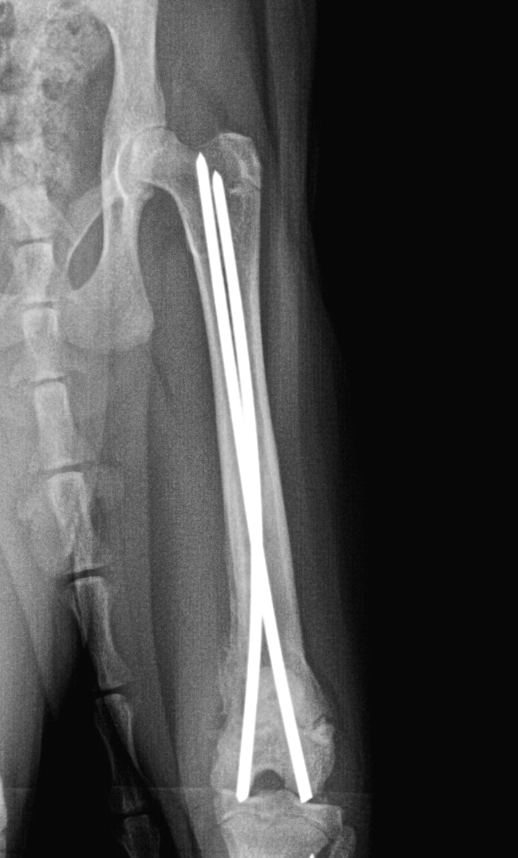

Fixation with pins | Metal rods inserted through the bone or into the medullary cavity | Straighten and temporarily hold a simple fracture. Fix a small fragment. Fracture near a joint | Diaphyseal fracture in a young animal. Articular fracture |

Criterion | Plates & screws | External fixators | Pins / nails |

Stability | Excellent | Medium to excellent | Medium |

Invasiveness | Requires opening the bone site | Percutaneous placement | Less invasive |

Operative time | Medium to long | Short to medium | Short |

Typical use | Diaphyseal fractures, osteotomies, TPLO, arthrodeses | Open, infected fractures, joint sprains | Simple or articular fractures |

Equipment | Lots of costly equipment: plates, screws, guides, drills, screwdrivers | Little equipment: pins, rods, clamps, tightening wrenches | Little equipment: smooth or threaded pins, pin cutter, cerclage wire |